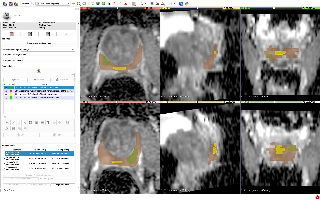

## PDMR-833975-119-R

| 名称 | 标注内容 | 类型 | 模态 | 数量 | 标签格式 | 文件格式 |

| - | - | - | - | - | - | - |

| [PDMR-833975-119-R](https://wiki.cancerimagingarchive.net/display/Public/Imaging+tissue+characterization+of+a+patient+derived+xenograft+model+of+adenocarcinoma+pancreas%3A+PDMR-833975-119-R) | 胰腺癌 | | MRI | 20 | | dcm |

[Aistudio下载](https://aistudio.baidu.com/aistudio/datasetdetail/64052)